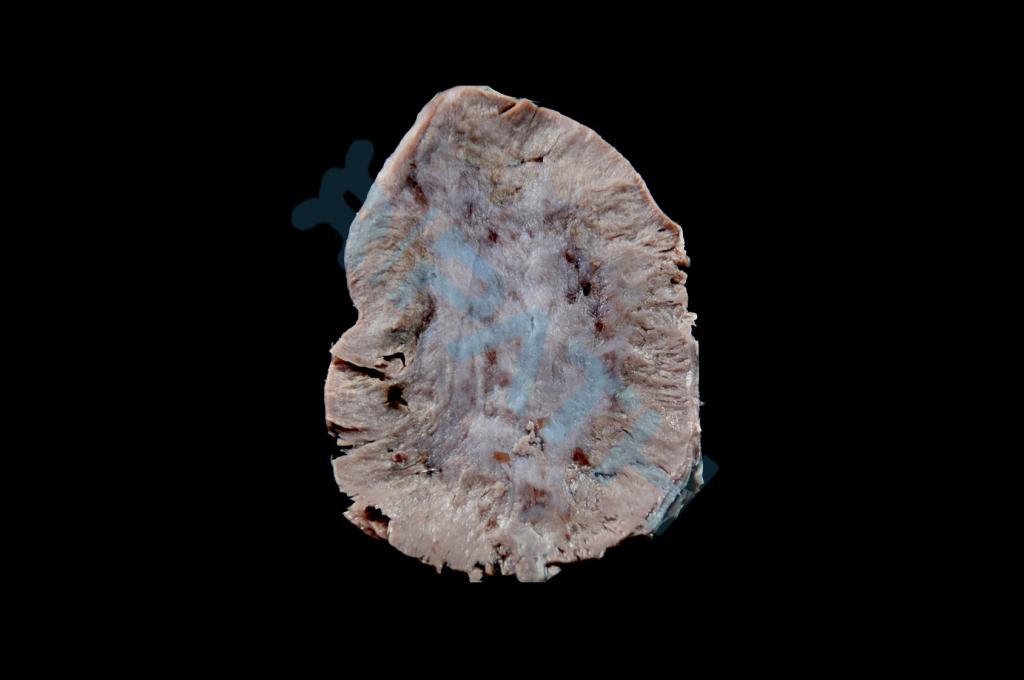

肝癌(多结节型)